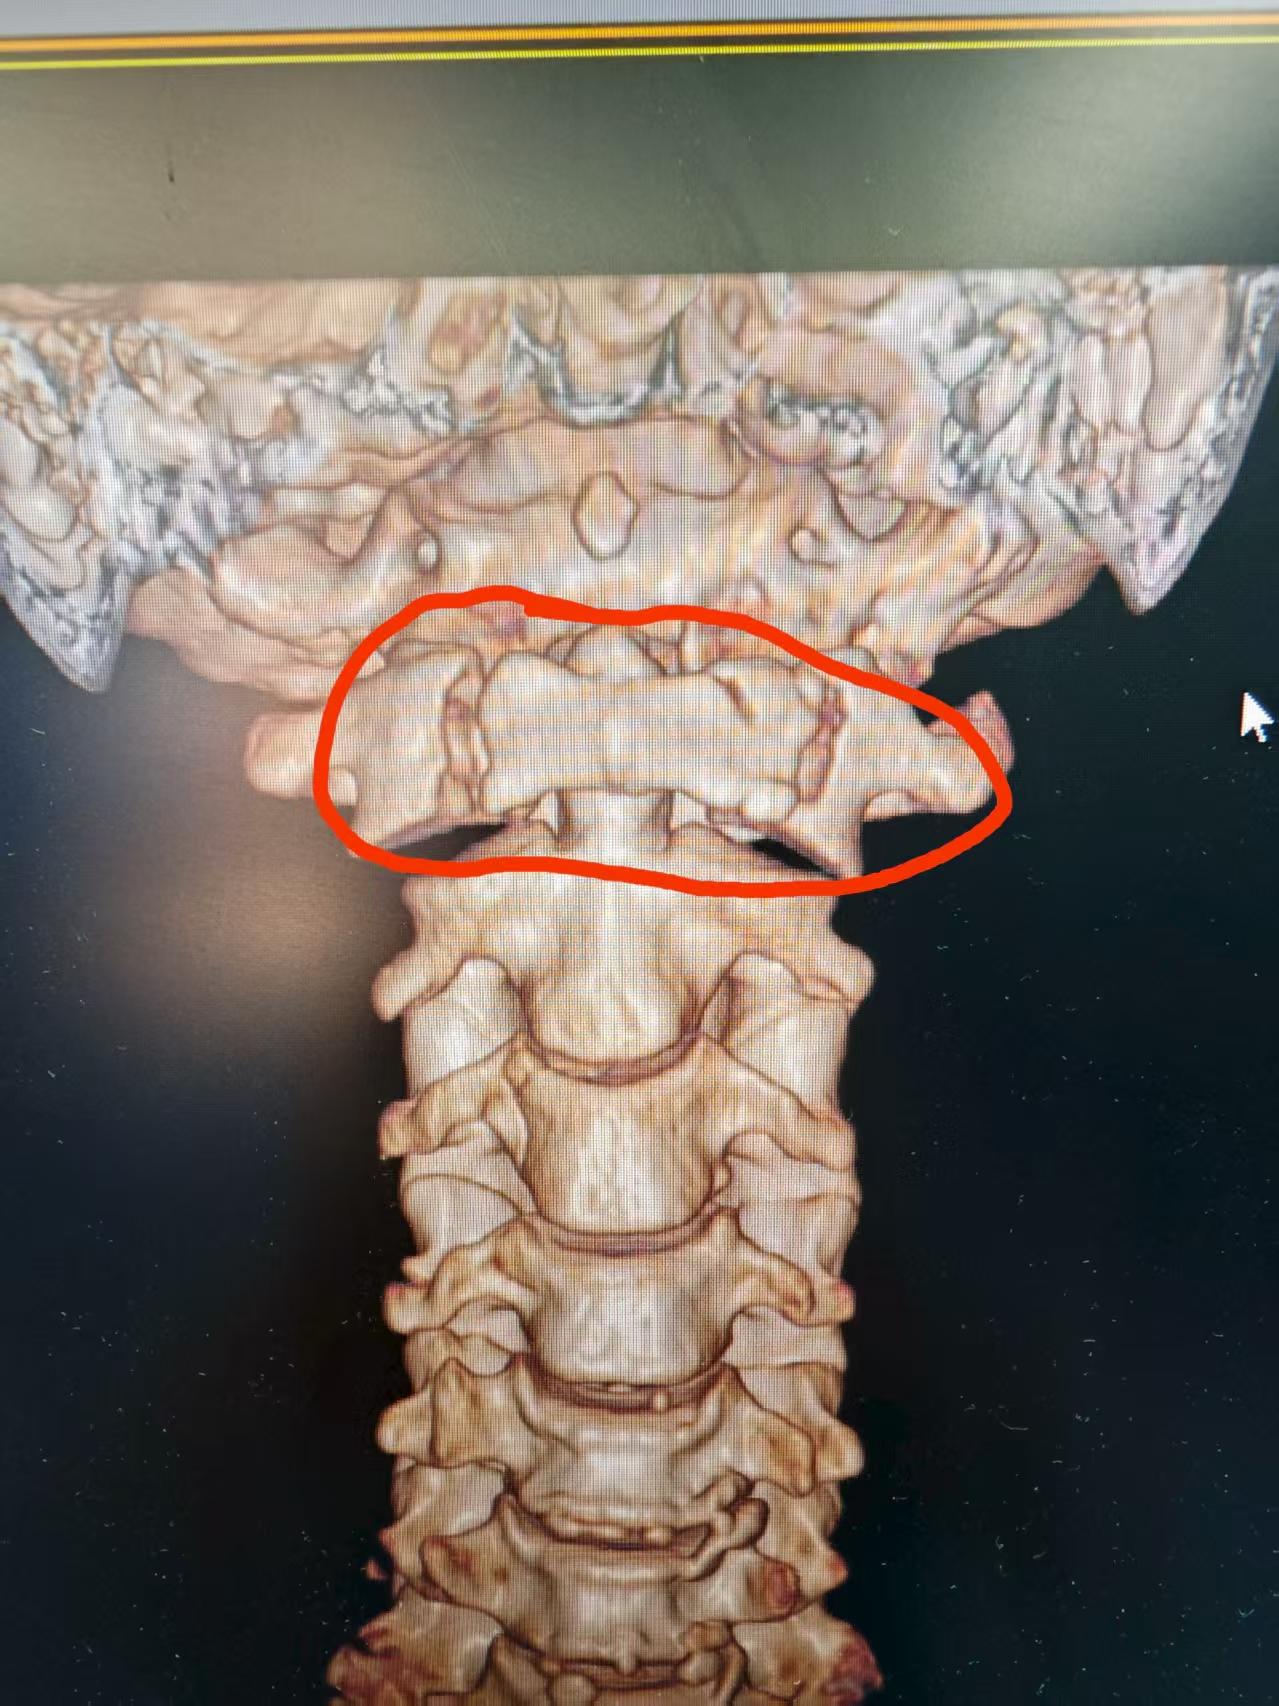

寰枢椎手术素有“脊柱外科珠峰”之称。接诊后,太和人民医院骨科主任骆新波带领团队迅速展开评估。由于邝阿姨存在血管畸形、骨质发育畸形,手术风险陡增,稍有不慎损伤神经血管,可能造成严重后果。为确保安全,团队术前反复分析三维CT等影像资料,

还借助多种高精度检测仪器,精准规划寰枢椎椎弓根螺钉植入路径。